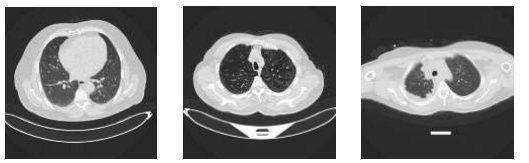

We use the IQ-OTH/NCCD dataset [iqoth_dataset], comprising 11971197 CT images labeled as Normal (416), Benign (120), and Malignant (561). Figure 1 shows representative samples; Figure 2 illustrates class distribution.

Figure 1: Representative CT samples for (left to right): Benign, Normal, Malignant.